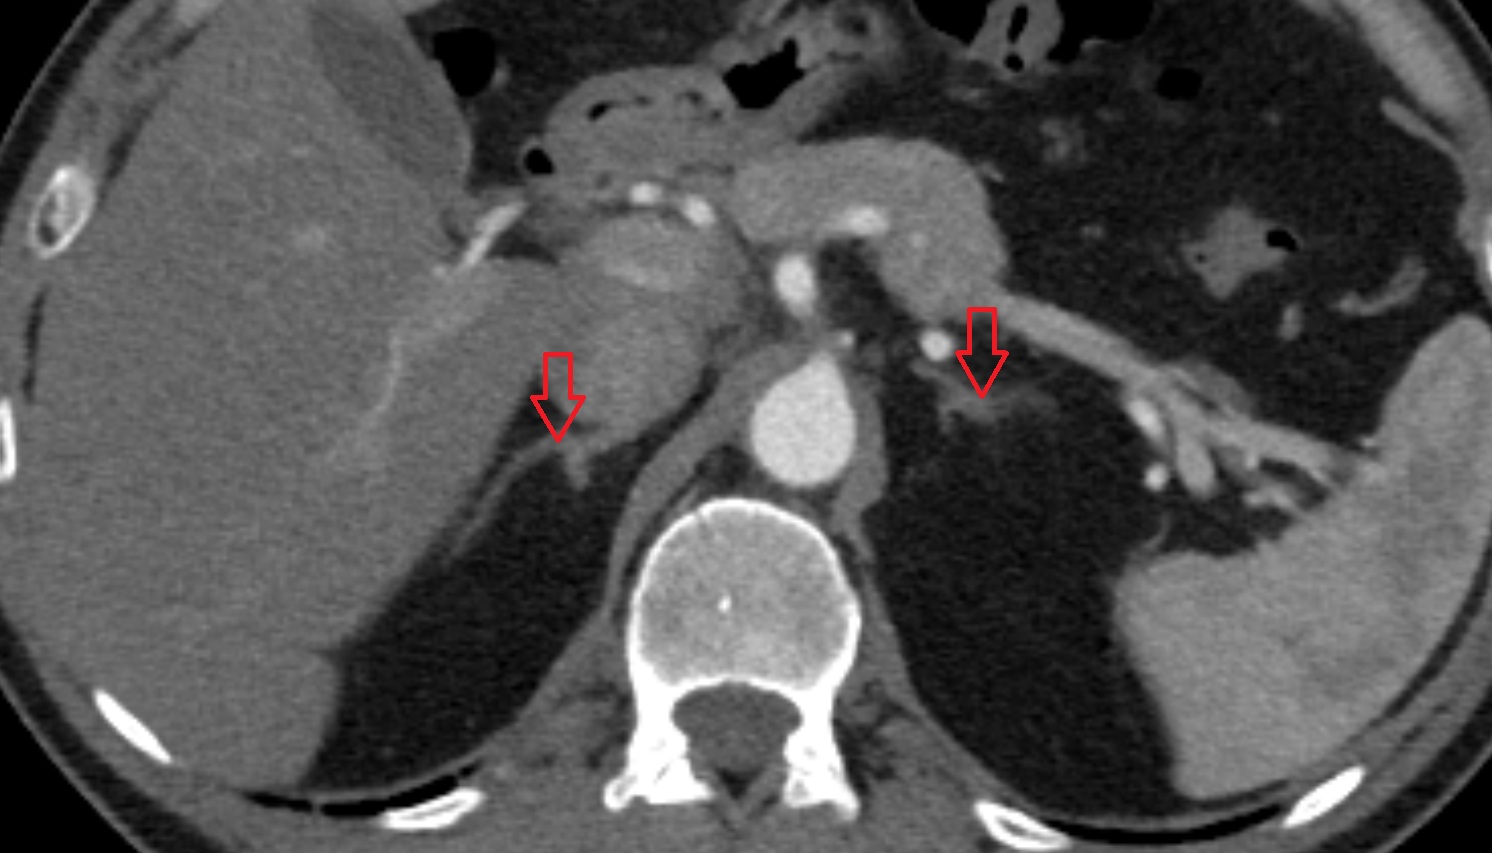

- Right adrenal gland

- Left adrenal gland

- Adrenal glands

- Right kidney

- Left kidney

- Adrenal gland